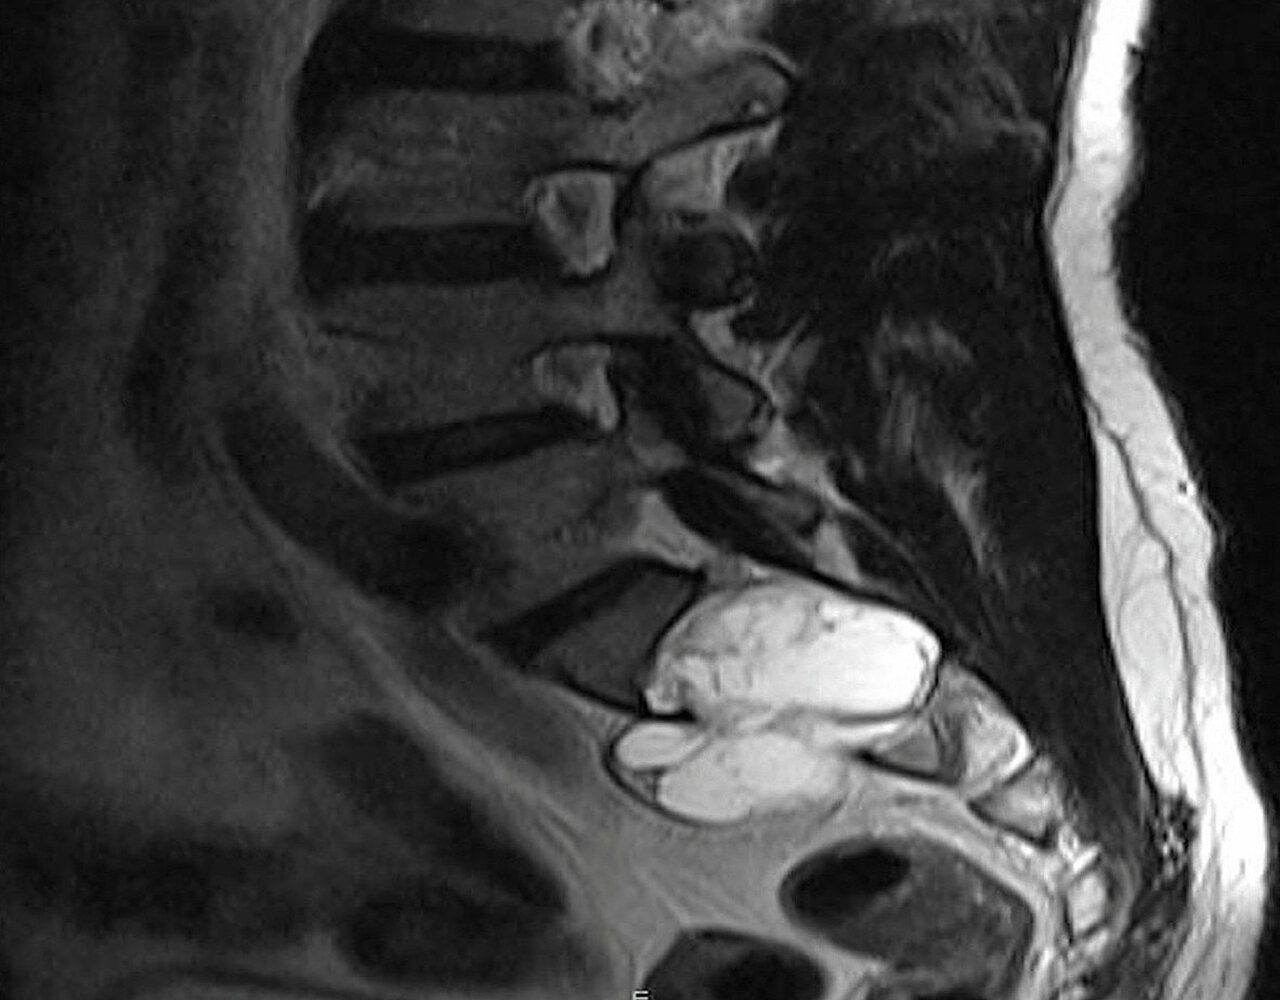

Fall 2

Ein 43-Jähriger klagt über diffuse Schmerzen im linken Bein, sensible Störungen und passagere Lähmungserscheinungen. Erst die CT-gesteuerte Biopsie konnte die Diagnose Schwannom sichern. Der benigne Tumor im Os sacrum zeigte ein retroperitoneales und intraspinales Wachstum. Auch bei diesem Patienten gelang eine vollständige Exzision – allerdings nur über einen nach ventral erweiterten dorsalen Zugang. Die betroffene S1-Nervenwurzel links konnte geschont werden. Auch dieser Patient hat nach dem Eingriff keine Beschwerden und keine neurologischen Ausfälle mehr.